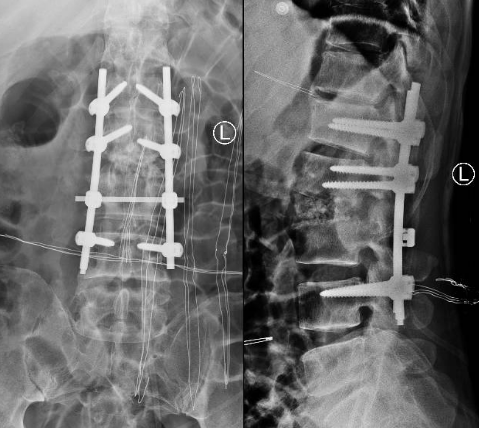

术后X线片

患者出院后感腰部疼痛持续加重,到少妇色情 门诊就诊,以“腰椎感染”收住入院。患者发病后腰椎CT及MRI均提示腰2-3椎间隙变窄,椎板破坏,综合以上资料诊断”腰椎结核”。入院后经口服四联抗结核药物治疗3周,患者自觉腰部疼痛减轻,午后无发热及盗汗后,在全麻下行颈后路病灶清除、椎间植骨、椎弓根钉棒系统内固定术。手术顺利,术后继续抗结核治疗。患者恢复顺利,术后1周下床活动,无特殊不适。术后2周拆线、出院,院外继续口服抗结核药物治疗,定期门诊复查。